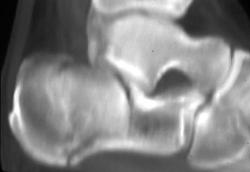

3D of Carpal Bones